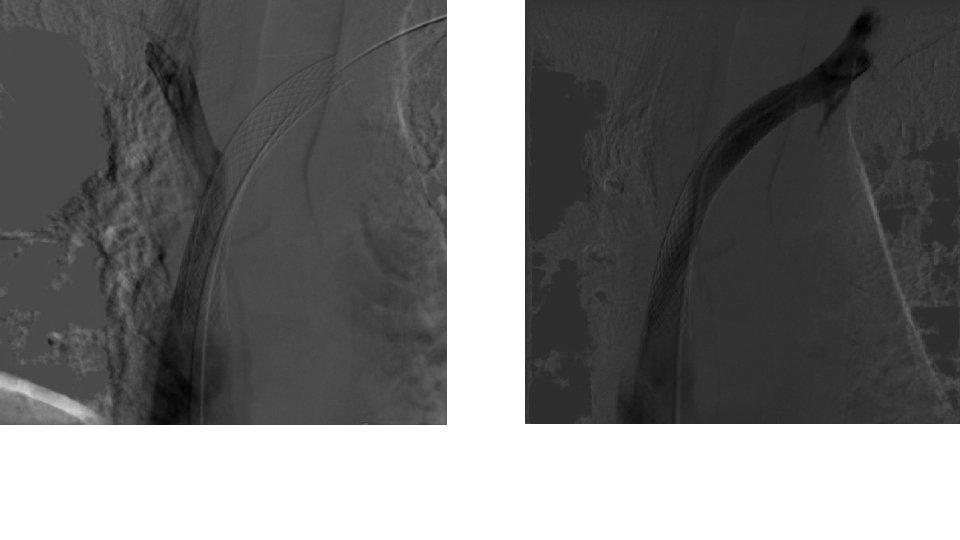

Only 3. 0 mm PTA balloon could cross the stenosis and required high pressure inflation. Sequential PTA with 5. 0 mm balloon

• Initial angiography after 5. 0 mm PTA to rule out immediate complications. • No complications were noted.

After IVUS. High pressure angioplasty with 10. 0 mm PTA balloon was required to overcome the severe fibrotic nature of stenosis.

16 x 60 WALLSTENT was deployed and postdilated with a 16 mm PTA balloon